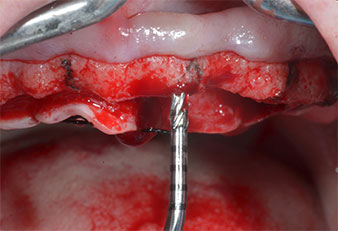

A flame-shaped, diamond-coated piezoelectric instrument (Piezomed I1) was used to mark the implant positions and to perform pilot preparation (Fig. 3). Care was taken to use an up and down movement, with reduced power, full irrigation and low pressure (below 300 g). Next a pilot instrument (Piezomed I2A/I2P) was applied for the initial 2 mm diameter enlargement of the implant sites (Fig. 4), followed by a 3 mm insert (Fig. 5).

Ultrasonic marker instrument Piezomed

Fig. 3: Preparation with the ultrasonic marker instrument Piezomed I1 is performed in an up and down movement, parallel to the long axis of the working part.